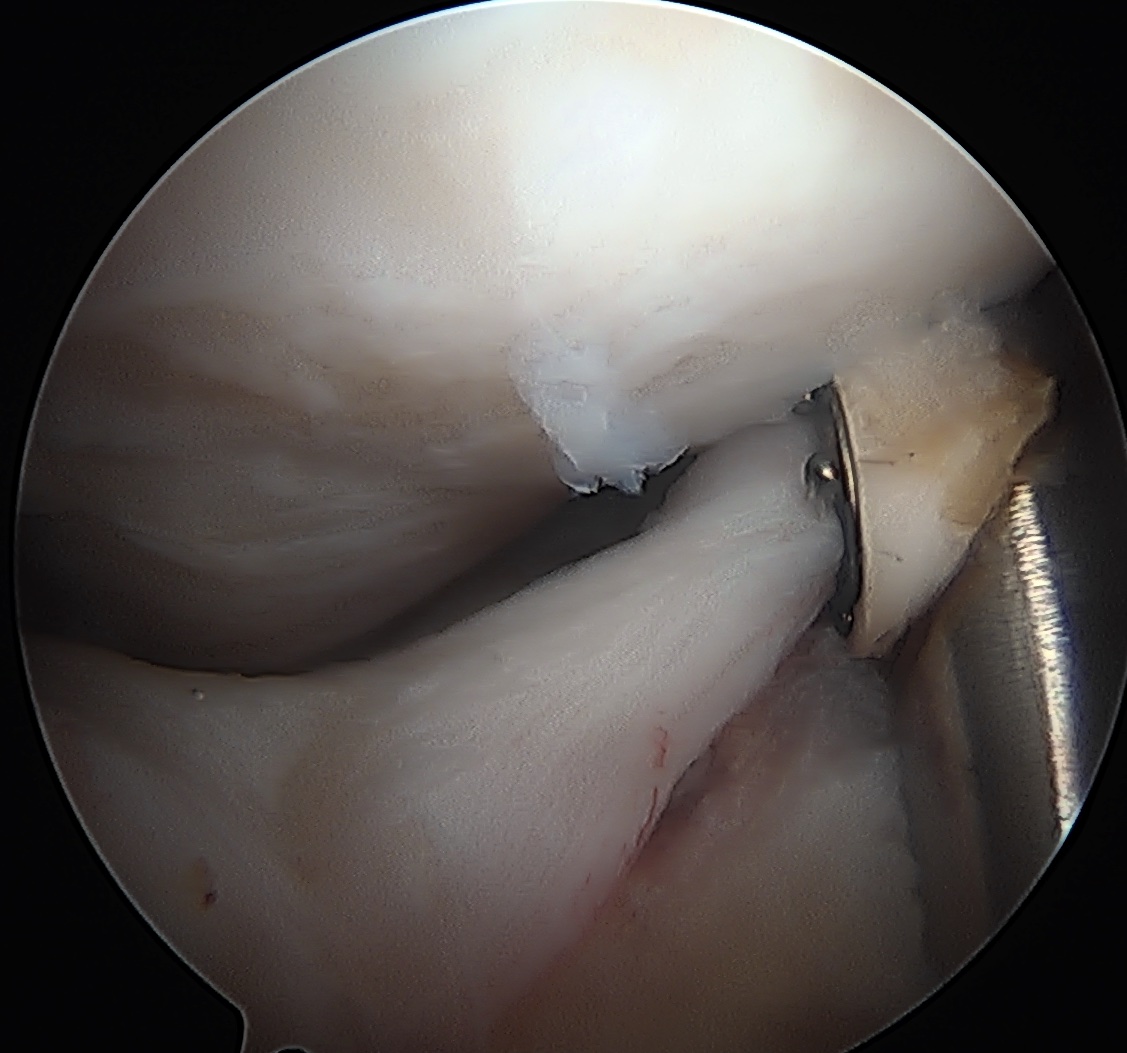

CAM resection

Capsule

- distal capsule suspension sutures / parachute technique

- T capsulotomy - better for large Cam lesions, needs repair

Placing distal capsule sutures to allow parachute technique / distal capsule suspension to expose Cam

T capsulotomy to expose large Cam at head neck junction